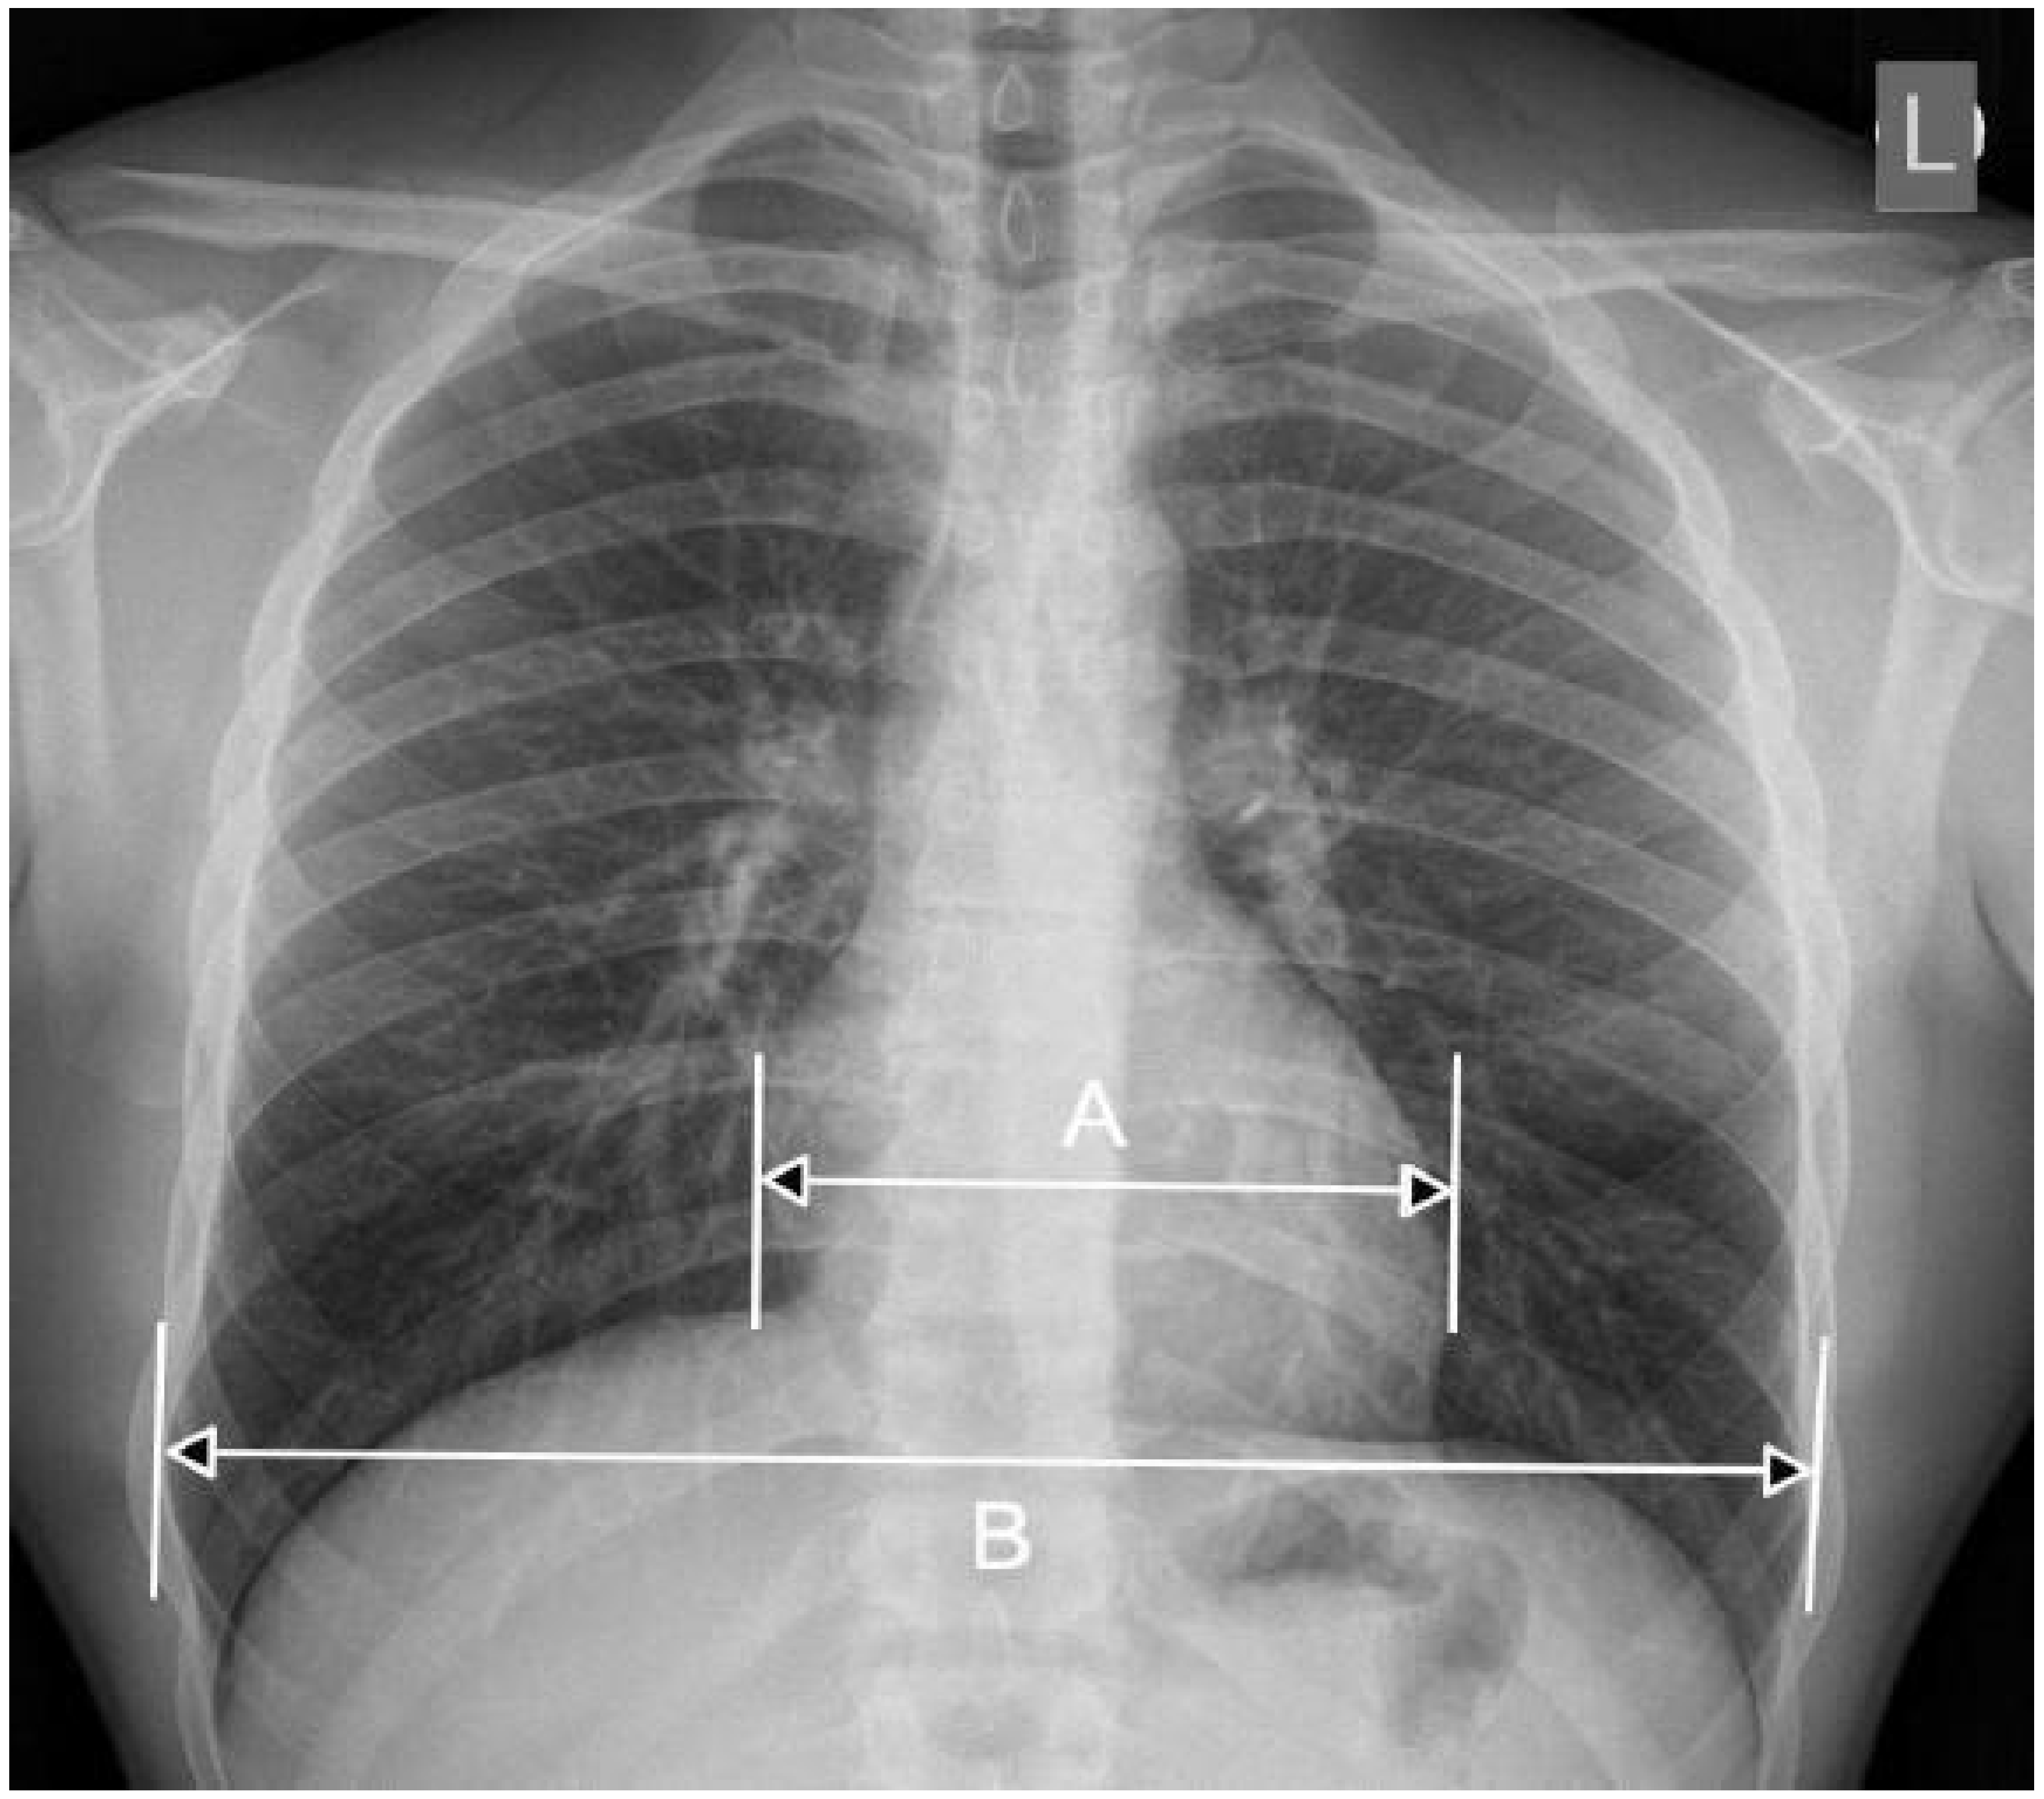

- CXR: The visualization of the heart’s size and shape, often used as a preliminary diagnostic tool. Moreover, the Cardiothoracic Ratio (CTR) is a diagnostic metric utilized to identify cardiomegaly (an enlarged heart) in CXRs captured in the posteroanterior (PA) view. In order to determine this ratio, the maximum horizontal diameter of the heart is divided by the maximum horizontal diameter of the thoracic cavity, which is measured at the inner edges of the ribs. An average CTR ranges from 0.42 to 0.50. A CTR exceeding 0.50 is indicative of cardiomegaly, thus signaling the presence of an enlarged heart. For a visual representation, refer to Figure 2, which demonstrates a sample CXR used for CTR calculation.

Figure 2.

The approach to calculating the CTR involves measuring the relationship between the transverse diameter of the heart (denoted as [A]) and the transverse diameter of the chest cavity (denoted as [B]), as observed on a chest radiograph taken in the posteroanterior (PA) view. The CTR is then computed using the following formula: CTR = A/B [7].